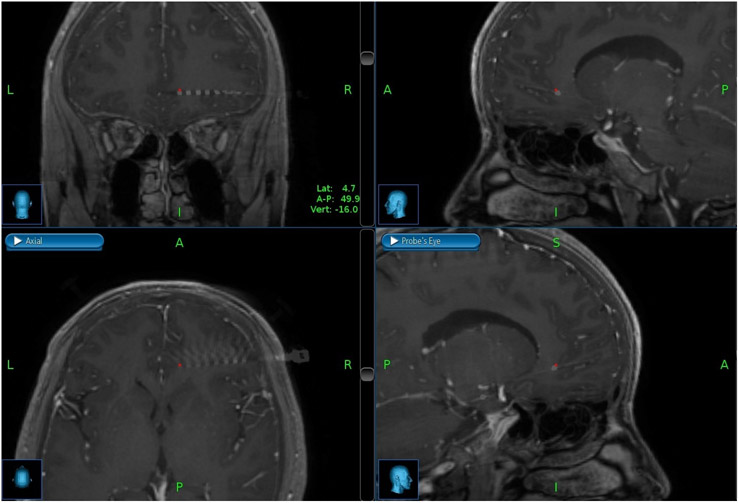

AD-TECH (Oak Creek, WI) depth electrodes, each with 8-10 macro ring-style contacts having a diameter of 1.1mm, length of 1.57mm, and center-to-center pitch 10mm, were implanted in each patient. Implanted electrode locations were confirmed with post-surgical CT imaging merged with pre-operative MRIs. Figure 1 shows merged CT/MRI images for a representative patient (2) in the sagittal, coronal, transverse, and probe’s-eye planes in the OFC. The NeuroPort™ Neural Signal Processor (Blackrock Microsystems, Salt Lake City, UT) was used to record the local field potentials (LFP). LFP data was digitally sampled at 2,000 samples/sec with 16 bits and 250nV resolution from the macro contacts in the gray matter of the OFC. Recording contacts were referenced to a quiet white matter contact identified by a study epileptologist during neural signal acquisition. Table 2 details characteristics of the implanted electrodes in each patient, including the number of electrodes in the OFC.

Figure 1.

Merged CT/MRI images for a representative patient in coronal, sagittal, axial, and probe’s eye planes within the orbitofrontal cortex.